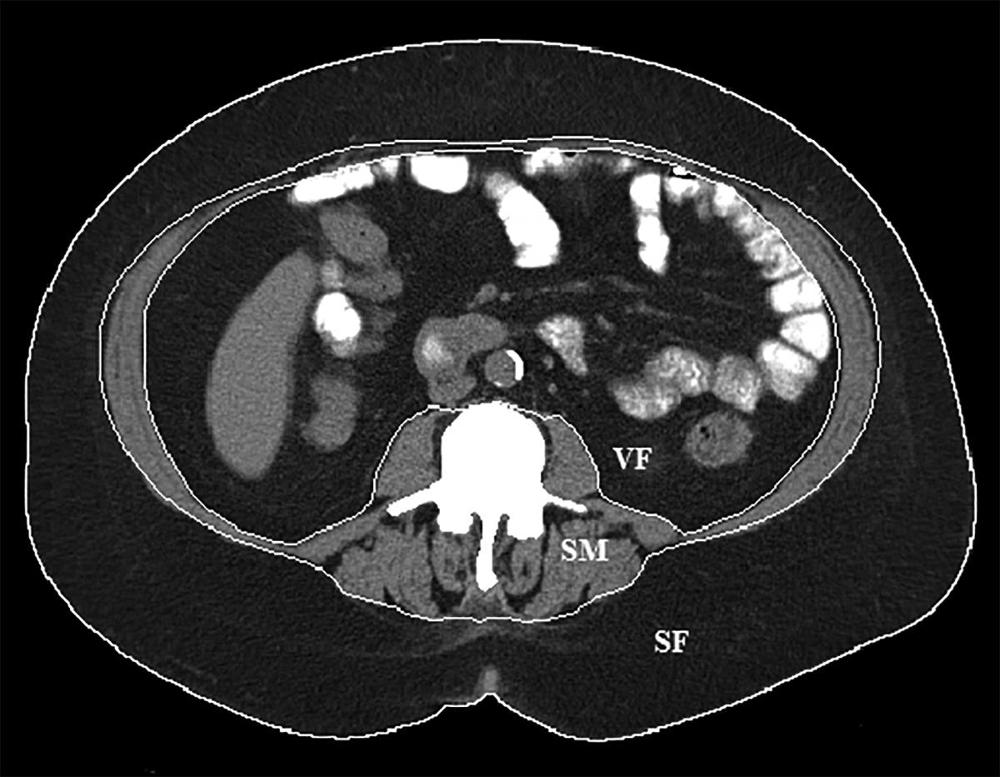

Figure 1. Body composition segmentation at the L3 lumbar vertebral body level. Boundaries for subcutaneous fat (SF), visceral fat (VF) and skeletal muscle (SM) are delineated by the white lines.